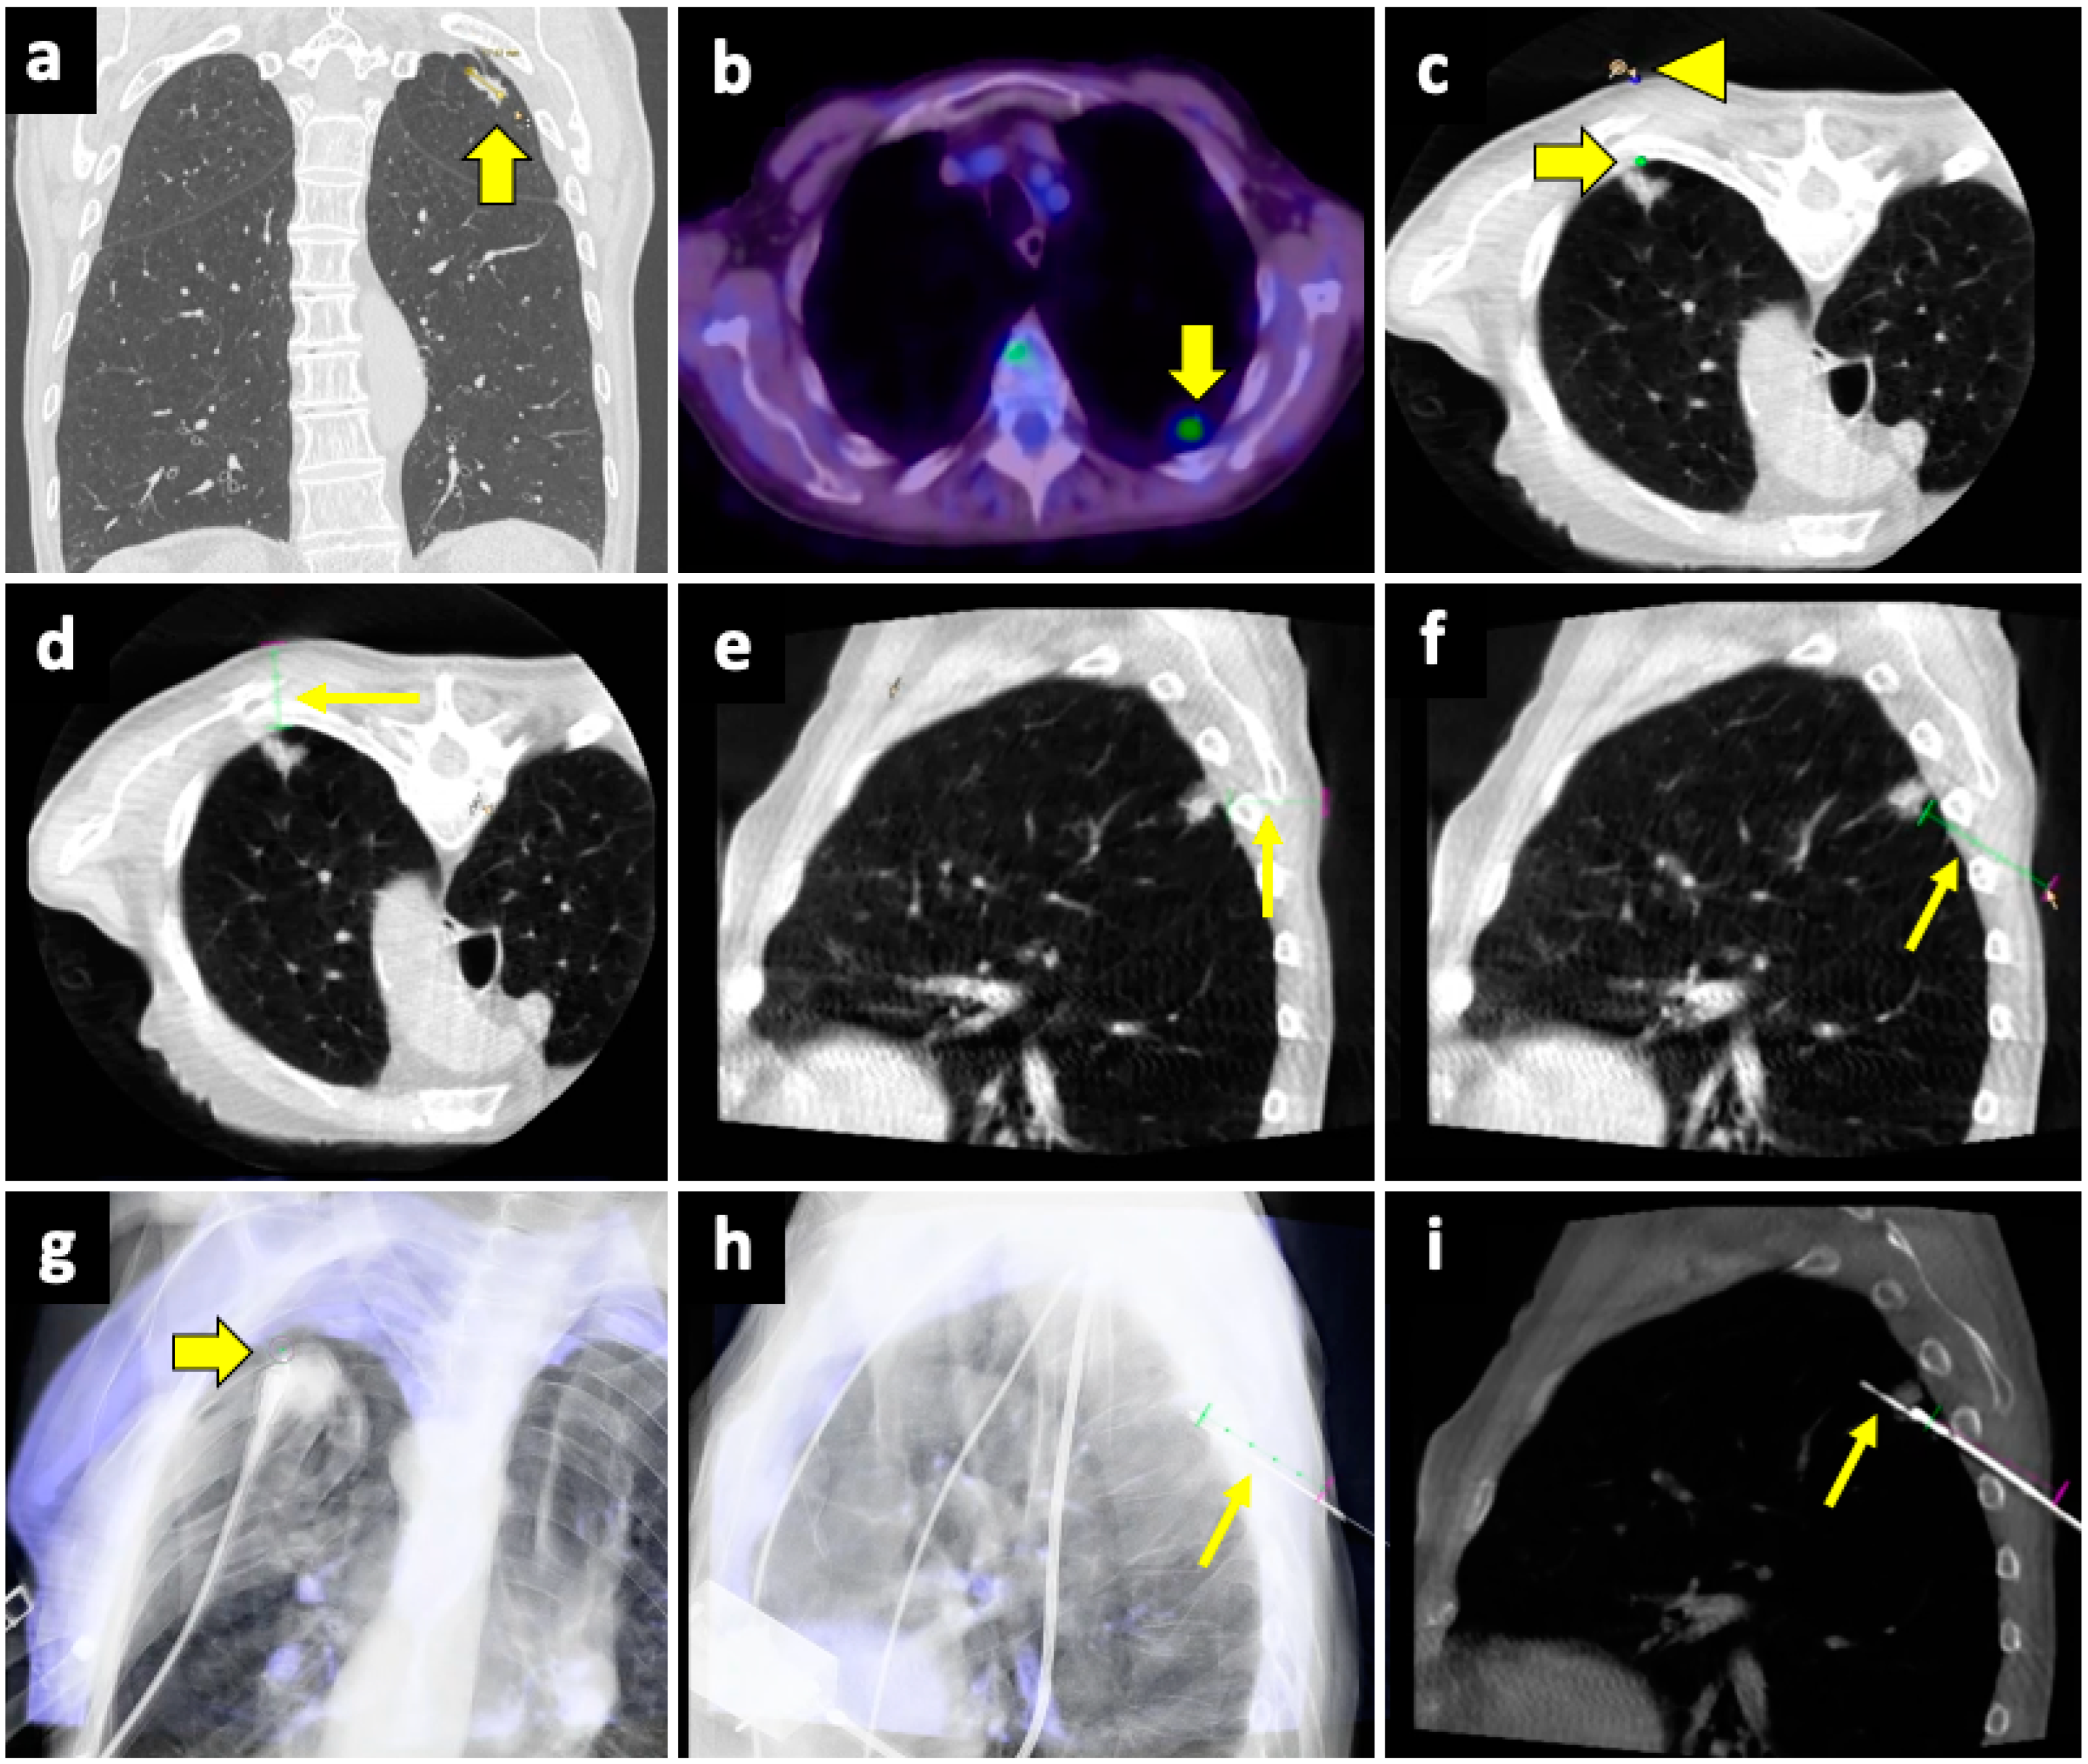

The CBCT system consists of flat-panel fluoroscopy and a CBCT scanner. The execution of CBCT-virtual-navigation-guided lung biopsy is performed in steps. The first step is to acquire a CBCT scan for adequate planning of the biopsy. Briefly, using the software (various software exist, by different vendors), the operator establishes the target lesion and the needle entry point at the skin surface, after which a virtual segment connecting the entry and target points is shown, representing the needle path. On the basis of this planning, the software automatically calculates the correct C-arm position to display the needle entry point on the patient’s skin. This phase of the procedure is called “entry point positioning”. After skin disinfection of the access area, under fluoroscopic guidance, the operator positions the needle tip at the cutaneous entry point, based on the CBCT image appearing on the monitor as a fusion of the 3D volume previously acquired using CBCT and the real-time fluoroscopy bidimensional plane. At this time, the C-arm rotates in the “progression view” position, perpendicular to the previous one. Then, the needle is advanced into the chest to reach the target point, following the virtual path previously determined and displayed on the monitor in real-time fluoroscopy. Then, a second CBCT scan is performed to verify the needle’s correct placement, and the biopsy is taken. A final scan is acquired to assess any complications [124]. An example of CBCT-guided biopsy is illustrated in Figure 4.